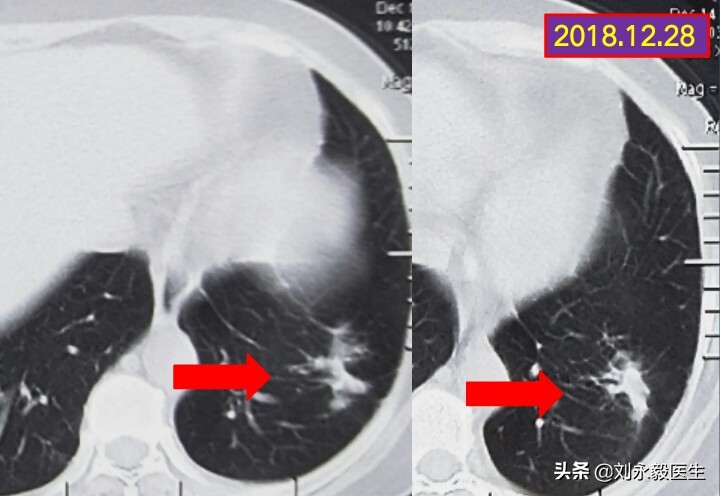

上图是一肺腺癌患者的胸部CT图,肿瘤位于左下肺,不是很大,没有胸水,病人生活自理、具有一般劳动能力,是刚发现的吗?不是!在2009年就被诊断为肺癌晚期,胸腔已有积液不能手术。近10年来经过“吉非替尼”临床研究性治疗,耐药后化疗多次,再次基因检测,T790M突变,奥西替尼(非正版)两年治疗……,若是当初放弃,结果会是什么样子呢?癌症,不要轻易放弃!